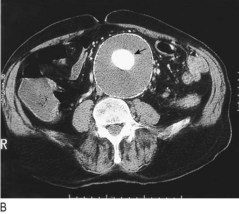

The arm: Axillary subclavian vein thrombosis can occur as a result of repetitive trauma at the thoracic outlet due to vigorous, repetitive exercise. Upper limb DVT may also complicate indwelling subclavian/jugular venous catheters. Symptoms include arm swelling and discomfort, often exacerbated by activity, especially when holding the arm overhead.

The arm is swollen and the skin is cyanosed and mottled, especially when dependent. Look for superficial distended veins (acting as collaterals) in the upper arm, over the shoulder region and on the anterior chest wall (Fig. 6.43).